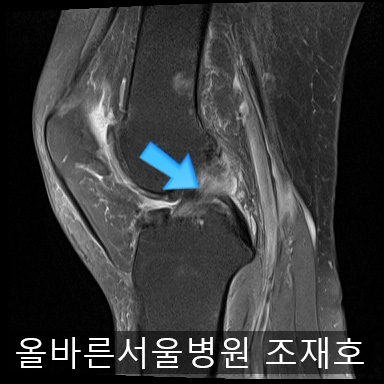

为了掌握具体情况拍了MRI。

内侧关节软骨几乎不见,软骨板也受损严重。软骨损伤部位充满关节液。

软骨板损伤严重

虽然前方十字韧带粘液样变性,但稳定性无异常